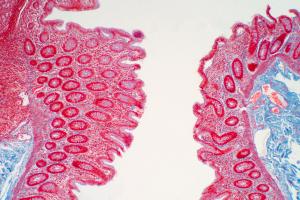

Les infections bactériennes sont d'ailleurs plus fréquentes chez les patients atteints de lymphome cutané dont la peau est plus fragile. Ces infections se multiplient avec le développement de la maladie. Le lymphome cutané à cellules T ou « T cutané » est caractérisée par une prolifération de cellules T malignes dans un environnement inflammatoire chronique. Avec la progression de la maladie, bactéries colonisent la barrière cutanée et la moitié des patients décède de l'infection plutôt qu'en raison de la malignité. Des données cliniques ont déjà montré le rôle direct des bactéries dans la progression de ce cancer. Cette étude décrypte les voies moléculaires de ce rôle bactérien.

In vitro, l'équipe montre à partir de prélèvements de tissus de peau affectée de patients atteints, et d'isolats bactériens qu'une toxine de Staphylococcus aureus (staphylococcal enterotoxin-A /SEA) stimule l'expression de 2 protéines, STAT3 et IL-17, dans les cellules T malignes ce qui favorise l'activation d'une voie oncogénique établie bien documentée dans le développement du cancer (carcinogenèse). En bref, via ses toxines, la bactérie « profite » aux cellules cancéreuses et favorise leur croissance. Dans le lymphome cutané, des cellules immunitaires spécifiques, les lymphocytes T CD4+ se transforment en cellules cancéreuses. L'étude montre que les toxines des bactéries permettent aux cellules cancéreuses d'envoyer des signaux qui perturbent le mécanisme de défense immunitaire, qui normalement devrait lutter contre les cellules cancéreuses. Les bactéries pourraient donc contribuer à rendre le lymphome de la peau soudainement plus agressif chez certains patients.